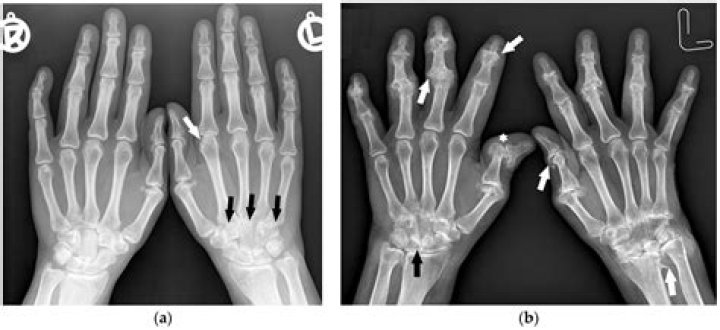

Medical imaging, including X-rays and magnetic resonance imaging (MRI), is crucial in diagnosing hip pain. An X-ray can reveal an excess of bone on the femoral head or neck and the acetabular rim. An MRI can reveal fraying or tears of the cartilage and labrum.

There is no single test for diagnosing osteoarthritis, but often it is diagnosed by an abnormal X-ray that shows characteristic features such as narrowing of the joint and spurring of the joint margins. Your doctor will take your medical history and perform a physical examination.